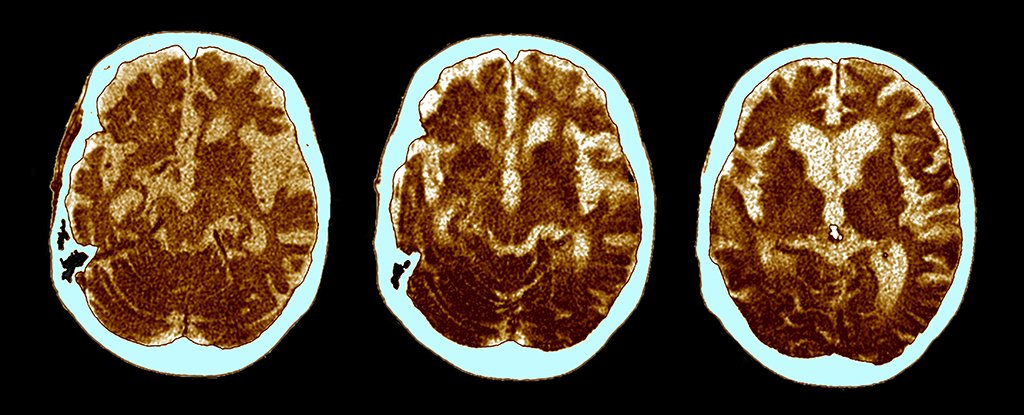

HomeMarkets Markets The Hidden Cause of Alzheimer’s May Have Been Identified a Century Ago By news April 1, 2024 0 196 FacebookTwitterPinterestWhatsApp Alzheimer’s disease is commonly associated with clumps and tangles of proteins building up in brain cells. Yet for more than a century, accumulations …This post was originally published on this site Share FacebookTwitterPinterestWhatsApp Subscribe Login Notify of new follow-up comments new replies to my comments Please login to comment 0 Comments Inline Feedbacks View all comments Stay Connected149,452FansLike396,312FollowersFollow2,650SubscribersSubscribe Latest Articles Energy What is the Strait of Hormuz, and why does its closure matter so much to the global economy? Hot Items A Plan B for space? On the risks of concentrating national space power in private hands Energy Iran’s targeting of airport, ports and hotels in reaction to US strikes has forced Gulf nations onto front lines of a war – Hot Items Donald Trump has made some bold claims on the US economy. But how do they stack up against the data? Energy ‘Destruction is not the same as political success’: US bombing of Iran shows little evidence of endgame strategy Markets Toppling Tuesday – Regimes and Markets Edition Biotech RFK Jr. Lied His Way Into Office and American Health Is the Victim Markets Putin Is the Iran War’s One Sure Winner Markets Trump Makes Surreal Turn From Talking War to Mocking Melania AI The SaaSpocalypse Has Arrived…Or Has It? Markets Trump’s lethal presidency Markets Monday Market Mayhem – World War Trump and Portfolio Hedges Market News Deeply conflicted, Kushner represents the U.S. in high-stakes negotiations with Iran Markets Claude dethrones ChatGPT as top U.S. app after Pentagon saga Load more